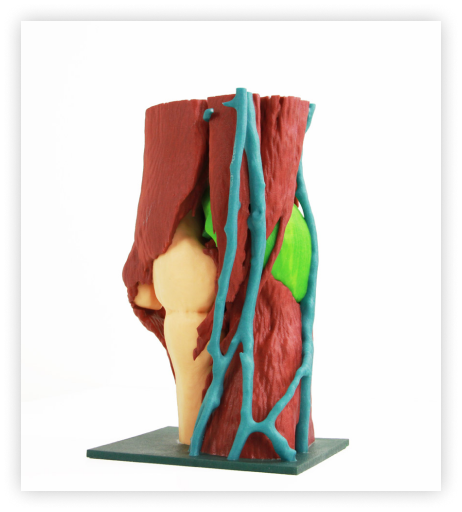

Asthi offers four types of models to suit a variety of surgical applications. Our coloured models provide a detailed and vivid representation of anatomical structures, while our transparent models allow for greater visibility and depth perception. Our bone-like models offer a Realistic simulation of human bone. Whether you’re a surgeon, medical student, or researcher, Asthi’s 3D-printed anatomical models offer a comprehensive solution for surgical planning and training.

Our transparent models are made from a clear, high-quality resin that allows you to see the internal structures of the human body. These models are perfect for studying the finer details of human anatomies, such as the location of blood vessels, nerves, and organs.

Our coloured models are designed to provide a more visual representation of human anatomy. They are available in various colours and are perfect for medical professionals who prefer a more visual learning style. These models are great for teaching, as the different colours make it easy to identify and study specific anatomies.